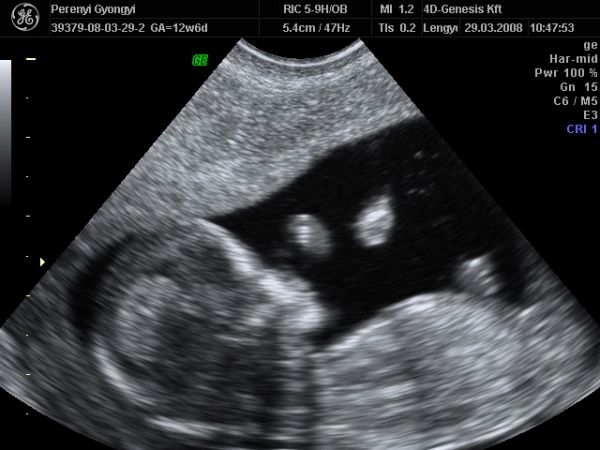

NHS-ben (TB kb), ami ingyen van 2db Uh van...12 és 20 hetesen. Ezen kívül minden hónapban találka a midwife-al, aki vizeletet néz, vérnyomást mér, megkérdezi hogy vagy, és elbeszélget veled, ha kérdésed, problémád, félelmed van. Aztán vannak a magán kórházak, ahova a középosztály felettiek járnak. Itt ugye annyit mehetsz, amennyit bír a pénztárcád, de mivel itt az előbbi a bevett szokás, sok nő nem kér semmi extrát. A privát ellátásért és szülésért viszont a végén kb egy 500-600 fontos számlát kapsz. Akire vigyázok, ő is ennyiért született. De ők nem kértek semmi extrát, 4D-re sem mentek el. Ja és aki NHS-re jár, de nem bír magával, az elmehet UH studiokba, amik a 4D-re mennek rá, de van 2D-s korai Uh is...mint pl majd én is leszek nagy valószínűség szerint.